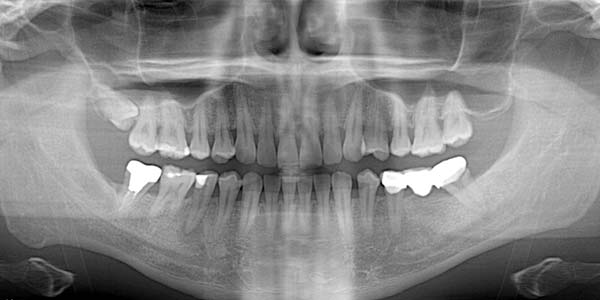

牙橋嚴重蛀牙,即拔即種,避免二次傷口 首頁 案例分享 人工植牙 牙橋嚴重蛀牙,即拔即種,避免二次傷口 多年前製作之牙橋,因為二度齲齒,導致支台齒蛀蝕,而需重新製作 牙橋支臺齒嚴重蛀牙 STEP1.拔除殘根並植入兩根植牙 STEP2.骨粉填補缺損骨頭缺陷 STEP3.三個月後,準備製作正式假牙 STEP4.正式假牙完成